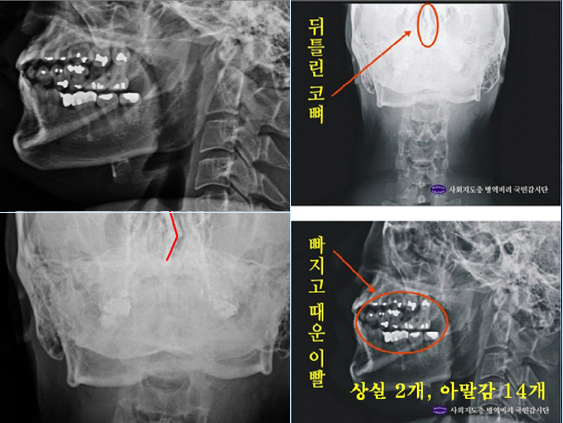

다른 하나는 자생병원에서 찍은 박주신씨의 엑스레이 치아사진을 보면, 아말감 치료를 받은 치아가 무려 14개나 된다는 점이다. 치과의사 문준식씨는 2005년 7월부터 2013년 8월까지 박주신씨를 치료했다고 주장했는데, 1990년대 이후 서울시에 있는 치과 중 아말감으로 이렇게 많은 치아를 치료한 경우는 거의 없다.

- ▲ ▲박주신씨 명의의 치아 엑스레이(X-Ray). 구외 X-Ray 상에 나타나는 각종 의혹은, 허리 MRI와 더불어 해당 피사체가 주신씨가 아닐 가능성에 무게를 더한다.ⓒ 사회지도층병역비리감시단

박주신 치과진료기록이 던지는 의문들박주신씨의 치과진료기록도 풀리지 않는 미스터리로 남아있다. 양승오 박사 등에 대한 검찰의 수사가 진행되던 지난해, 이 사건 피고인들은 박주신씨의 치아가 보이는 구외 X-Ray(이하 치아 X-Ray)를 근거로, 박주신씨의 신체를 촬영했다는 X-Ray 속 피사체가 제3의 인물일 가능성을 주장했다.

피고인들이 치아 X-Ray를 근거로, '피사체 바꿔치기' 의혹을 강하게 제기한 이유는, X-Ray에 나타난 치아의 상태가, 도저히 20대 중반 청년의 것이라고는 보기 힘든 특징을 갖고 있었기 때문이다.

주신씨 구외 X-Ray 사진을 보면, 치아 상태가 매우 불량하다는 사실을 알 수 있다. 치아 2개는 아예 없고, 아말감으로 때운 치아가 무려 14개에 달한다.

주신씨의 치아 아말감 치료와 관련돼, 김우현씨는 “혹자는 아말감 치료를 10개 이상 한 게 무슨 대수냐? 하면서 무시하는 경향이 있지만, 이는 모든 인과관계와 사실들을 무시하려는 것”이라고 비판했다.주신씨의 구외 X-Ray는 그가 허리 MRI를 촬영하면서 같이 찍은 X-Ray 사진들 중에서 치아가 보이는 X-Ray 사진이다.

따라서 구외 X-Ray 상에 나타나는 각종 의혹은, 허리 MRI와 더불어 해당 피사체가 주신씨가 아닐 가능성에 무게를 더한다.

주신씨의 구외 X-Ray 사진 상에 나타나는 의문들은, 양승오 박사 등이 주신씨의 병역비리 의혹을 제기하게 된 핵심 요인 중 하나였다.

치아의 치료상태는 매우 불량하고, 심지어 골반 X-Ray 사진에서는 골절된 뼈조각까지 발견됐다.주신씨의 것으로 알려진 치아 X-Ray 사진을 본 치의학 박사 C씨의 소견이다

“자료를 보면 2개의 이빨은 아예 없고, 아말감으로 때운 치아 14개가 보인다.

게다가 환자는 하악 1소구치(아래 어금니 앞쪽)까지 아말감으로 치료했다.

(젊은 사람이) 이런 경우는 매우 드물다.”“특히 전체적인 치료 상태를 보면, 소위 말하는 [야매]로 했을 가능성이 높다.

최근 국내에서 교육받은 치과의사의 치료라고 생각할 수 없을 정도다.

45번, 46번 보철 치료 및 치아 상실 문제에 있어서도 마찬가지다.

보철물로는 상당히 저렴한 비귀금속 합금을 사용한 것으로 보인다.

37번 치아는 아예 없는 상태로 방치하기도 했다.”“박주신의 가정환경을 고려하면, 이런 치료를 받았을 가능성은 1%도 안 된다.

서울 방배동에 거주했던 중산층 이상의 가정에서는 흔치 않은 상황이다.”